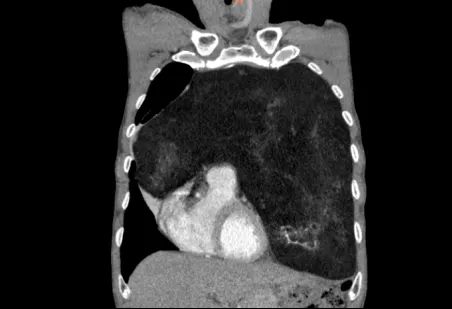

怀着忐忑的心情,家人陪同老人来到郑州大学第五附属医院胸外科就诊。完善胸部增强CT检查后,结果让经验丰富的高兴才主任也为之震惊:患者的前纵隔、左侧胸腔乃至部分右侧胸腔,被一个巨大的混杂密度团块所占据,其长径达23cm!这个巨大的瘤体几乎占满左侧胸腔,严重挤压纵隔使其向右移位,左肺因受压而萎陷。这正是导致老人长期胸闷、呼吸不畅的“罪魁祸首”。

面对这颗位置刁钻、体积巨大的肿瘤,手术切除是唯一有效的治疗手段,但风险极高。肿瘤毗邻心脏、大血管和肺组织,稍有不慎即可导致致命性大出血或重要脏器损伤。加之患者71岁高龄,心肺功能储备差,对麻醉和术后复苏提出了极大挑战。